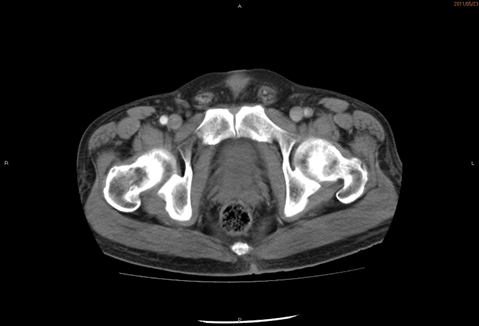

<造影CT>

診断は、急性下肢動脈閉塞。

腹部大動脈の総腸骨動脈分岐部より近位、さらに左総大腿~浅大腿動脈にも血栓像を認めました。